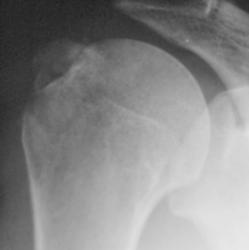

Травма. пациент направлен хирургом в рентгеновский кабинет для рентгенографии плечевого сустава. Были произведены рентгенограммы в двух проекциях. Могу представить, увы, только изображение в прямой проекции.

"Перелом-отрыв бугорка плечевой кости", так любят его наши травматологи, так и называют.

Соглашусь с коллегой Ореховым! Оторвался бугорок!

Ну, и по всей видимости, перелом, без смещения костных отломков.

Насчет линейной тени (две медиальные стрелки) - думаю, не перелом это, закрытая зона роста.

Однозначно, линия, указанная стрелками, это бывшая ростковая зона.

Вот то, что отмечено желтыми стрелочками на последней серии снимков - и есть отрыв большого бугорка. Такой большооооой отрыв большоооооооого бугорка.

Мое мнение, что анатомическая шейка плечевой кости абсолютно интактная! Пациент достаточно молод.